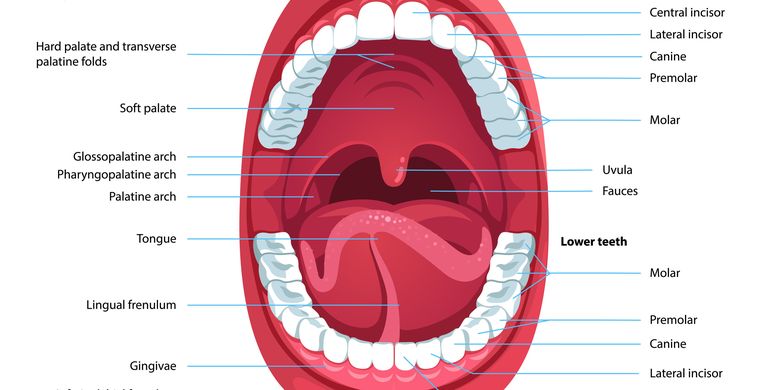

Mulut: Fungsi dan Strukturnya Halaman all - Kompas.com

Mulut: Fungsi dan Strukturnya Halaman all - Kompas.com

Prolog Materi - Mulut

Prolog Materi - Mulut